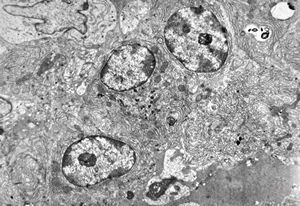

stomach- plasmocytoma